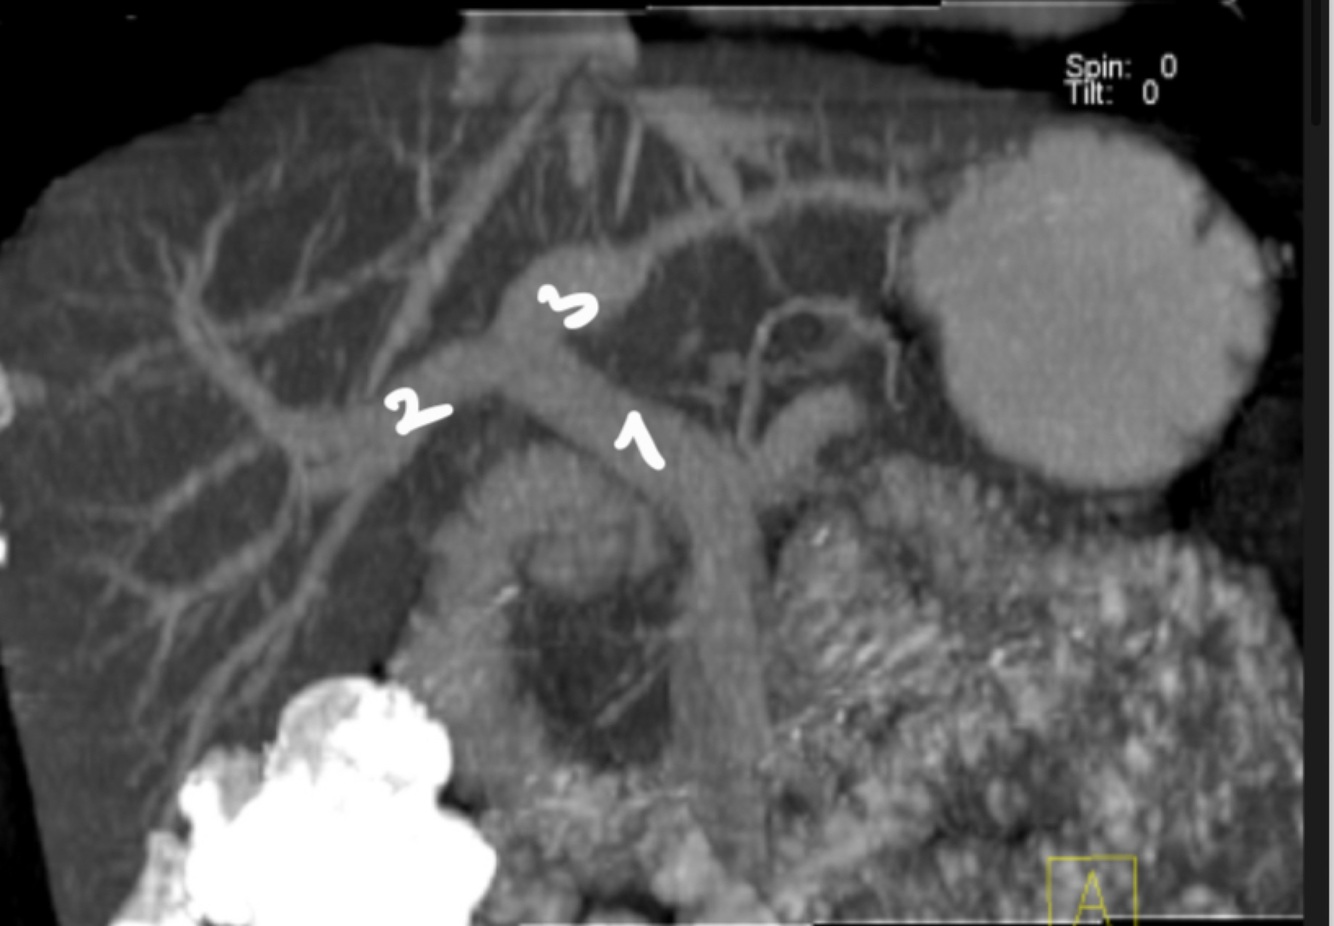

15

Q

Name those structures

A

1. Main portal vein

2. Right portal vein.

3. Left portal vein.

How well did you know this?